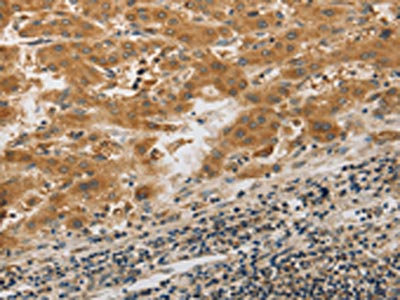

The image on the left is immunohistochemistry of paraffin-embedded Human colon cancer tissue using CSB-PA828391(PIBF1 Antibody) at dilution 1/20, on the right is treated with synthetic peptide. (Original magnification: ×200)

The image on the left is immunohistochemistry of paraffin-embedded Human liver cancer tissue using CSB-PA828391(PIBF1 Antibody) at dilution 1/20, on the right is treated with synthetic peptide. (Original magnification: ×200)